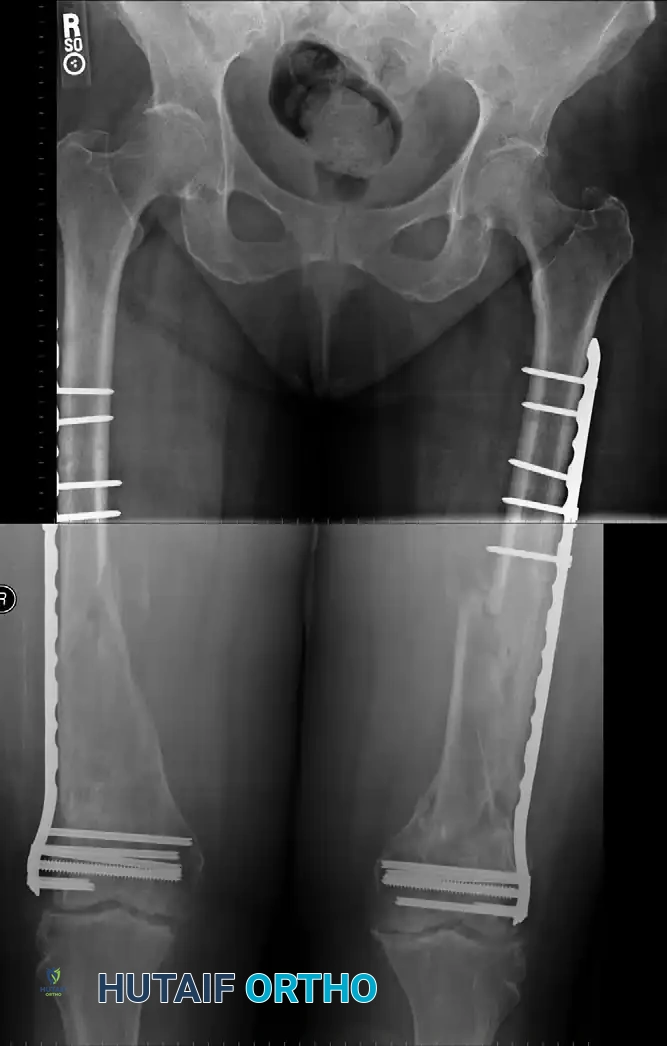

FIGURE 54-79: Polytraumatized patient with extensive pulmonary injuries and a femoral diaphyseal fracture treated with ORIF using large fragment compression plating to avoid medullary pressurization.

FIGURE 54-80A: Lateral radiographic view demonstrating a femoral shaft fracture stabilized with a broad plate and interfragmentary lag screws.

FIGURE 54-80B: Anteroposterior radiographic view of the same femoral shaft fracture, highlighting the restoration of axial alignment and the utilization of the 8-cortex rule proximal and distal to the fracture site.